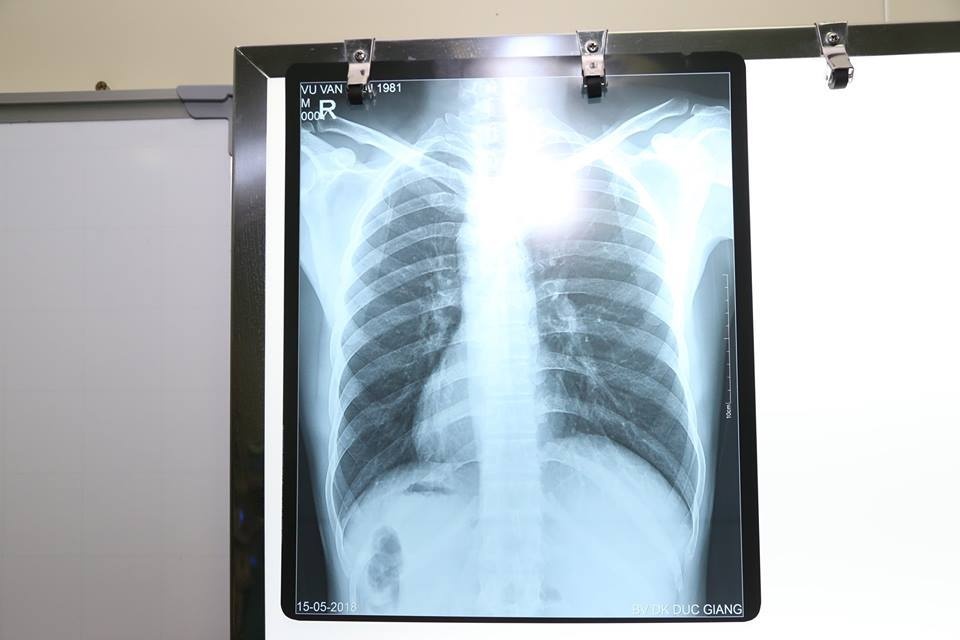

Bệnh nhân được đưa tới khoa Ngoại tổng hợp, Bệnh viện Đa khoa Đức Giang. Tại đây, qua thăm khám và làm các chỉ định cận lâm sàng như siêu âm ổ bụng, chụp X-quang, xét nghiệm máu… các bác sĩ rất bất ngờ với hình ảnh trái tim cùng với các phủ tạng khác trong lồng ngực và bụng của bệnh nhân H. ở vị trí "soi gương" so với bình thường. Trái tim và dạ dày ở bên phải, gan và ruột thừa thì ở bên trái.

| Phủ tạng bị đảo ngược hoàn toàn được thể hiện trên phim. |